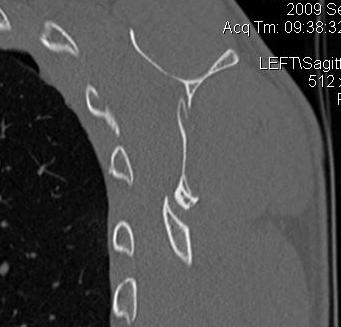

Combined Glenoid and Scapula Fractures

Case 1

- displaced glenoid fracture and neck fracture

- ORIF both through posterior / Judet approach